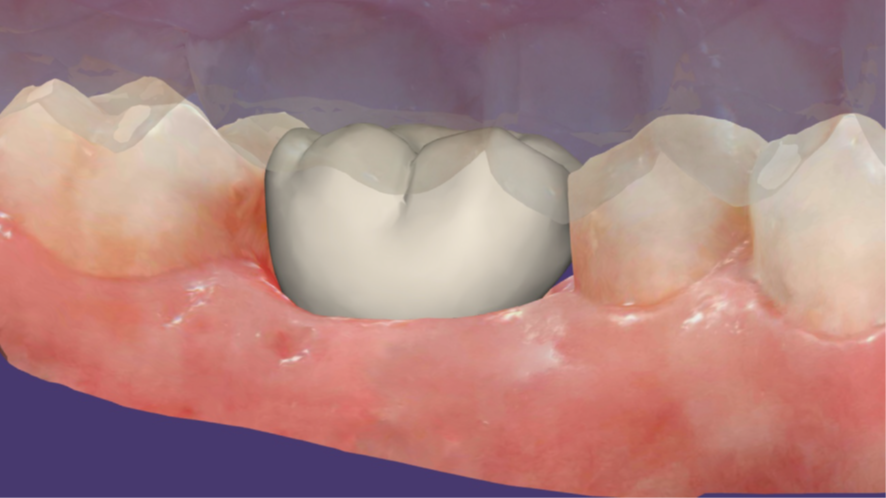

Agora, o laboratório de prótese consegue alinhar as malhas e fazendo a subtração da malha referente ao escaneamento do cicatrizador personalizado fora da boca, parafusado no análogo, temos exatamente o perfil de emergência adquirido pelo cicatrizador personalizado. Então, é realizado o CAD da coroa sobre implante (Figura 16), e após a fresagem em zircônia, acabamento, polimento e maquiagem, recebemos a coroa fresada em zircônia cimentada no pilar Base T (Figuras 17 e 18) pronta para ser instalada no implante. Logo após a instalação da coroa sobre implante (Figura 19), uma radiografia periapical foi realizada (Figura 20), a fim de confirmar a adaptação correta da coroa sobre implante.